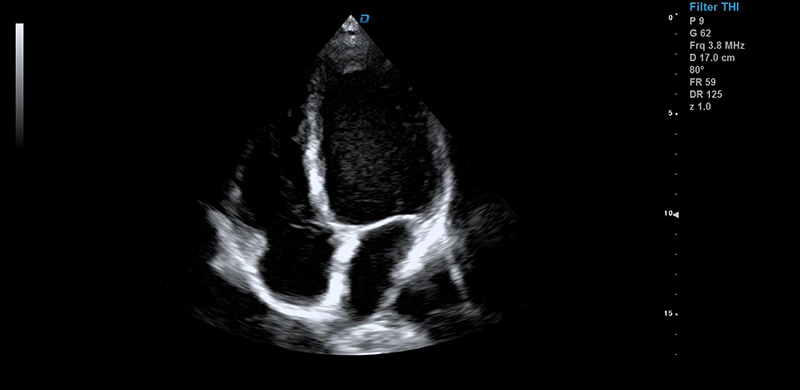

解剖3M成像技術:解剖3M成像比M型單線模式增加了3條解剖線,測量點角度可調,可得到心臟各個結構更多、更準確的信息,有利于更好的觀察心腔大小及室壁階段性運動的異常情況。

諧波成像(THI)、諧波融合成像(FHI):THI和FHI比傳統的信號處理得到的信號強度增加30%以上,降低了噪聲和偽像,大幅度提高組織圖像的分辨力